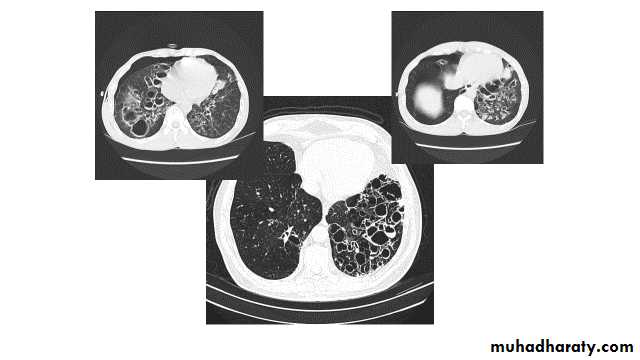

Bronchiactasis

Bronchiectasis refers to abnormal dilatation of the bronchial tree and is seen in a variety of clinical settings. CT is the most accurate modality for diagnosis. It is largely considered irreversibleCauses of bronchiactasias very important to consider

Plain radiograph

Chest x-rays are usually abnormal1. Tram-track opacities are seen in cylindrical bronchiectasis, and

2. air-fluid levels may be seen in cystic bronchiectasis.

Honey comb shadow

3.Overall there appears to be an increase in bronchovascular markings, and bronchi seen end on may appear as ring shadows .

4.Pulmonary vasculature appears ill-defined, thought to represent peri bronchovascular fibrosis .